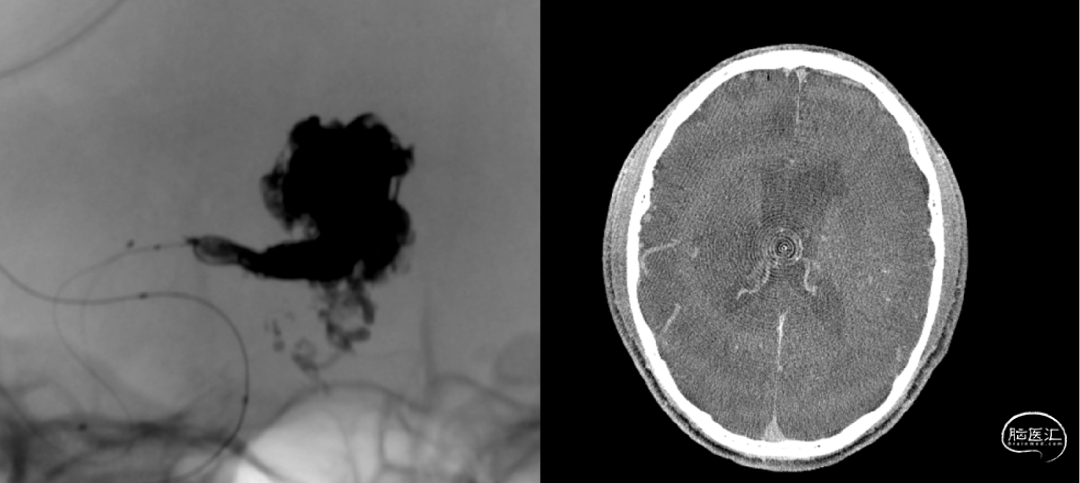

经Apllo微导管注入Onyx胶

术后造影脑动静脉畸形消失

术后CT未见出血及梗塞